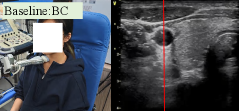

Figure 5: Real-World Experiment - Snapshots and ultrasound images, the red lines are the output of our pretrained regressor. No red line means the network can not detect the artery position. First row: UltraDP. (a) The policy began, and the artery was on the right of the image; (b) The policy output actions to guide the robot to make the artery center while going upwards; (c) The policy detected the bifurcation of the artery; (d) The external and internal arteries were clear in the image, and the scanning was over. Second row: Baseline, behavior cloning. (e)-(h): The BC policy (baseline 1) did not center the artery; And in the end, the policy drove the probe away from the neck, showing the unsatisfying generalization ability. Third row: Baseline, visual serving. (i)-(l) The VS controller (baseline 2) had the ability to center the artery; however, because some parameters like offset_z did not suit the female, the probe detached her neck, and the regressor couldn’t work when the image was incomplete; at last the probe kept going up, losing the image and hit her in the jaw.